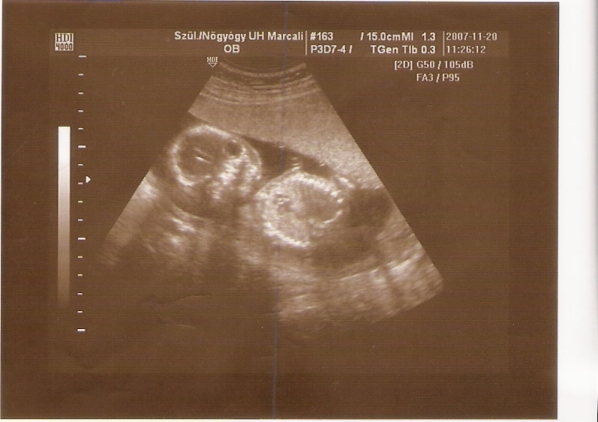

mi is voltunk 12. héten de akkor még csak 48mm volt a csöppem ezért rá egy hétre ujra és ime a képen a kis akrobata már 64 mm..majdnem 2 cm egy hét alatt